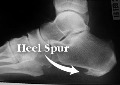

خار پاشنه چیست؟

تفکر بسیار شایعی در بین مردم و حتی پزشکان رواج دارد که درد پاشنه به علت خار پاشنه است. گرچه خیلی از افرادی که فاسئیت پلانتار دارند برجستگی کوچک استخوانی در زیر استخوان پاشنه دارند که به آن خار پاشنه میگویند، توجه به این نکته مهم است که علت درد، خار پاشنه نیست. وجود یک برجستگی استخوانی در زیر استخوان پاشنه علت درد آن ناحیه نیست همانطور که با خارج کردن این برجستگی استخوانی درد از بین نمیرود. از هر ده نفر یک نفر خار پاشنه دارد ولی همه آنها درد ندارند.